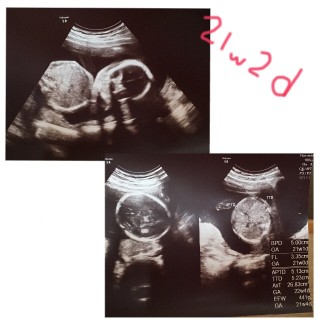

写真:21w2d:にきゆずさん

今日は検診の日でした! 1ヶ月前の検診で性別は女の子って 言われたのですが今日は良く見えなくて!笑 とりあえず旦那様に似て鼻が高いかな~ って!笑

480g!後ろ向いてて今日は顔見えないねーと諦めかけてたら動いて見せてくれました!^^胎動も感じるようになって可愛いさ倍増!